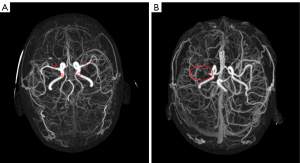

The First Affiliated Hospital of Chongqing Medical University provided the CTA and NCCT images used as the source data for training and testing the proposed deep learning model. In our study, the primary objective was to identify and categorize instances of intracranial LVOs, with a specific focus on occlusions occurring in the bilateral internal carotid arteries (ICAs) and the first segment of the bilateral middle cerebral artery (MCA-M1). To maintain the targeted approach of our work and ensure the precision of our results, we established strict criteria for patient inclusion based on the location of the vascular occlusion. Patients with vascular occlusions located outside of these predefined arterial segments were excluded. Ultimately, 435 patients were included after patients with poor image quality and those whose vascular blockage location did not match the research scope were excluded. Among these patients were healthy controls, while the remaining 159 were patients (64 with right MCA occlusion, 28 with right ICA occlusion, 47 with left MCA occlusion, and 20 with left ICA occlusion). All CTA scans were performed with a SOMATOM Definition Flash CT scanner (Siemens Healthineers, Erlangen, Germany). The typical acquisition parameters were as follows: voltage, 120 kVp; exposure, 250 mAs; slice thickness, 0.75 mm; and pitch, 0.8. Contrast-enhanced images were obtained with a 70- to 100-mL bolus of iodinated contrast medium at a rate of 4–5 mL/s. This study employed a stratified sampling approach for data partitioning to ensure experimental rigor. Initially, we employed stratified sampling to randomly select 20% of the samples from each category in the original dataset to form an independent test set. Following this extraction, data augmentation techniques were applied offline to augment the data volume for categories with fewer samples. Subsequently, the dataset was divided into training and validation sets in an 8:2 ratio. Figure 7 presents the final dataset generation process used in this study. To acquire the raw data, we first employed hospital workstation equipment to remove interference from superfluous information, such as that related to the skull. We then obtained images of the cerebral vessels using maximum density projection processing on a computer. Finally, the case-level categorization labels and pixel-level responsible vessel annotation tasks were completed by three radiologists with extensive clinical expertise, each with over 5 years of experience in neurovascular imaging. Annotations were aggregated through a consensus approach, in which the initial independent annotations were followed by blinded reviews and group discussions to resolve any discrepancies, ensuring the reliability and accuracy of the final labels.

In this study, we further created heat maps of model predictions using heat map visualization technology (42) to aid clinicians in understanding the rationale underlying the deep models’ conclusions. This technique is a form of visual explanation that gathers components helpful for categorization through the attention mechanism and compiles them into an interpretable support set. This produces a high-weight region at the image level, enhancing model transparency. Examples of the decision-making criteria used by our proposed model and various comparison approaches are shown in Figure 9. The first row of the figure depicts the original image with the occluded responsible vessel area outlined in red, which we hope the model will learn to use as a foundation for decision-making. The visualization of all approaches is shown in each column of images under the same categorization, with areas in deeper shades of red denoting more persuasive evidence. The figure also shows that all algorithms had roughly four vessel areas as their evidence centers in the heat map column for healthy controls. The most effective algorithm is class-balanced focal loss (CB-Focal), followed by MBF-Net, despite it having a smaller total range. However, MBF-Net (with AAGM) outperformed the other methods for occluded vessel evidence areas. Although some algorithms’ focus areas did include target areas (the regions marked in red in the original image), their focus center positions (the regions with the reddest shading) were noticeably off. It would be challenging for clinicians to appreciate that the deep models do truly provide prediction results based on critical area information if all the occlusion prediction outcomes are inadequate. When different vessels are blocked, MBF-Net (with AAGM) offers greater difference information. The position of the focus center can be adjusted within a suitable range depending on the occluded arteries. This demonstrates the effectiveness of our proposed model algorithm.